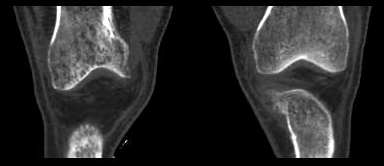

右侧股骨下端 胫骨近端及髌骨见骨质疏松,松质及皮质见虫蚀状溶骨性破坏,皮质变薄,骨小梁减少模糊,胫骨近侧干骺端内侧骨破坏性,关节肿胀,关节间隙增宽,周围未见明显软组织肿块.

就膝关节的病变,我还是支持wawaquan版主的意见,病理上可以解释为长期的关节炎性病变,充血引起的骨质疏松!!多发骨髓瘤好发于扁骨,再说,发生于长骨的多为一骨多病灶,象这样关节两端,骨质改变相同的少见!软组织变化也不支持.

考虑为缺血性改变。股骨远端及胫骨近端均呈同样改变,髓腔及骨皮质均未见骨破坏改变。

无积液,皮质变薄、小梁纤细无中断,骨干变细,周围肌群明显萎缩,不支持mm,也不支持滑膜慢性充血所致骨质疏松,故首先考虑废用性局限性骨质疏松,请结合临床查找疼痛原因。